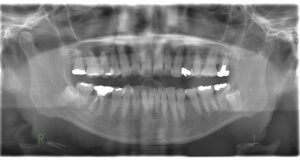

初診時のレントゲンです。一番後ろの歯のさらに奥に親指のような形のようなものが見えます。これが顎の関節です。左右一対で対照的な形を本来はしています。向かって左は丸く普通の形をしていますが、右の顎の関節の形は左に比べて小さくなっています。左のかみ合わせの高さが低くなっていることで、下顎が右の奥に押し込まれています。そのことで顎の関節が年月をかけて変形していると考えられます。顎の関節が定位置にいられないことで顎の開閉口でカクっと鳴ったり、痛みを生じます。顎関節症の原因にはいろいろな原因が考えられていますが、かみ合わせが原因とされる顎関節症のメカニクスは述べた通りです。顎の関節の後ろには血管、神経が通っています。顎の関節が後ろに押し込まれることでその部分を圧迫してしまいます。その圧迫が片頭痛の原因になっていることもあります。ほうれい線もかみ合わせの高さが低くなっている方が深くなります。左右差が出るのはこういった理由です。かみ合わせ高さを含めて改善され、下顎が本来の位置に戻ることができれば、時間はかかりますが顎関節の形は年齢に関係なく戻っていくと報告されています。